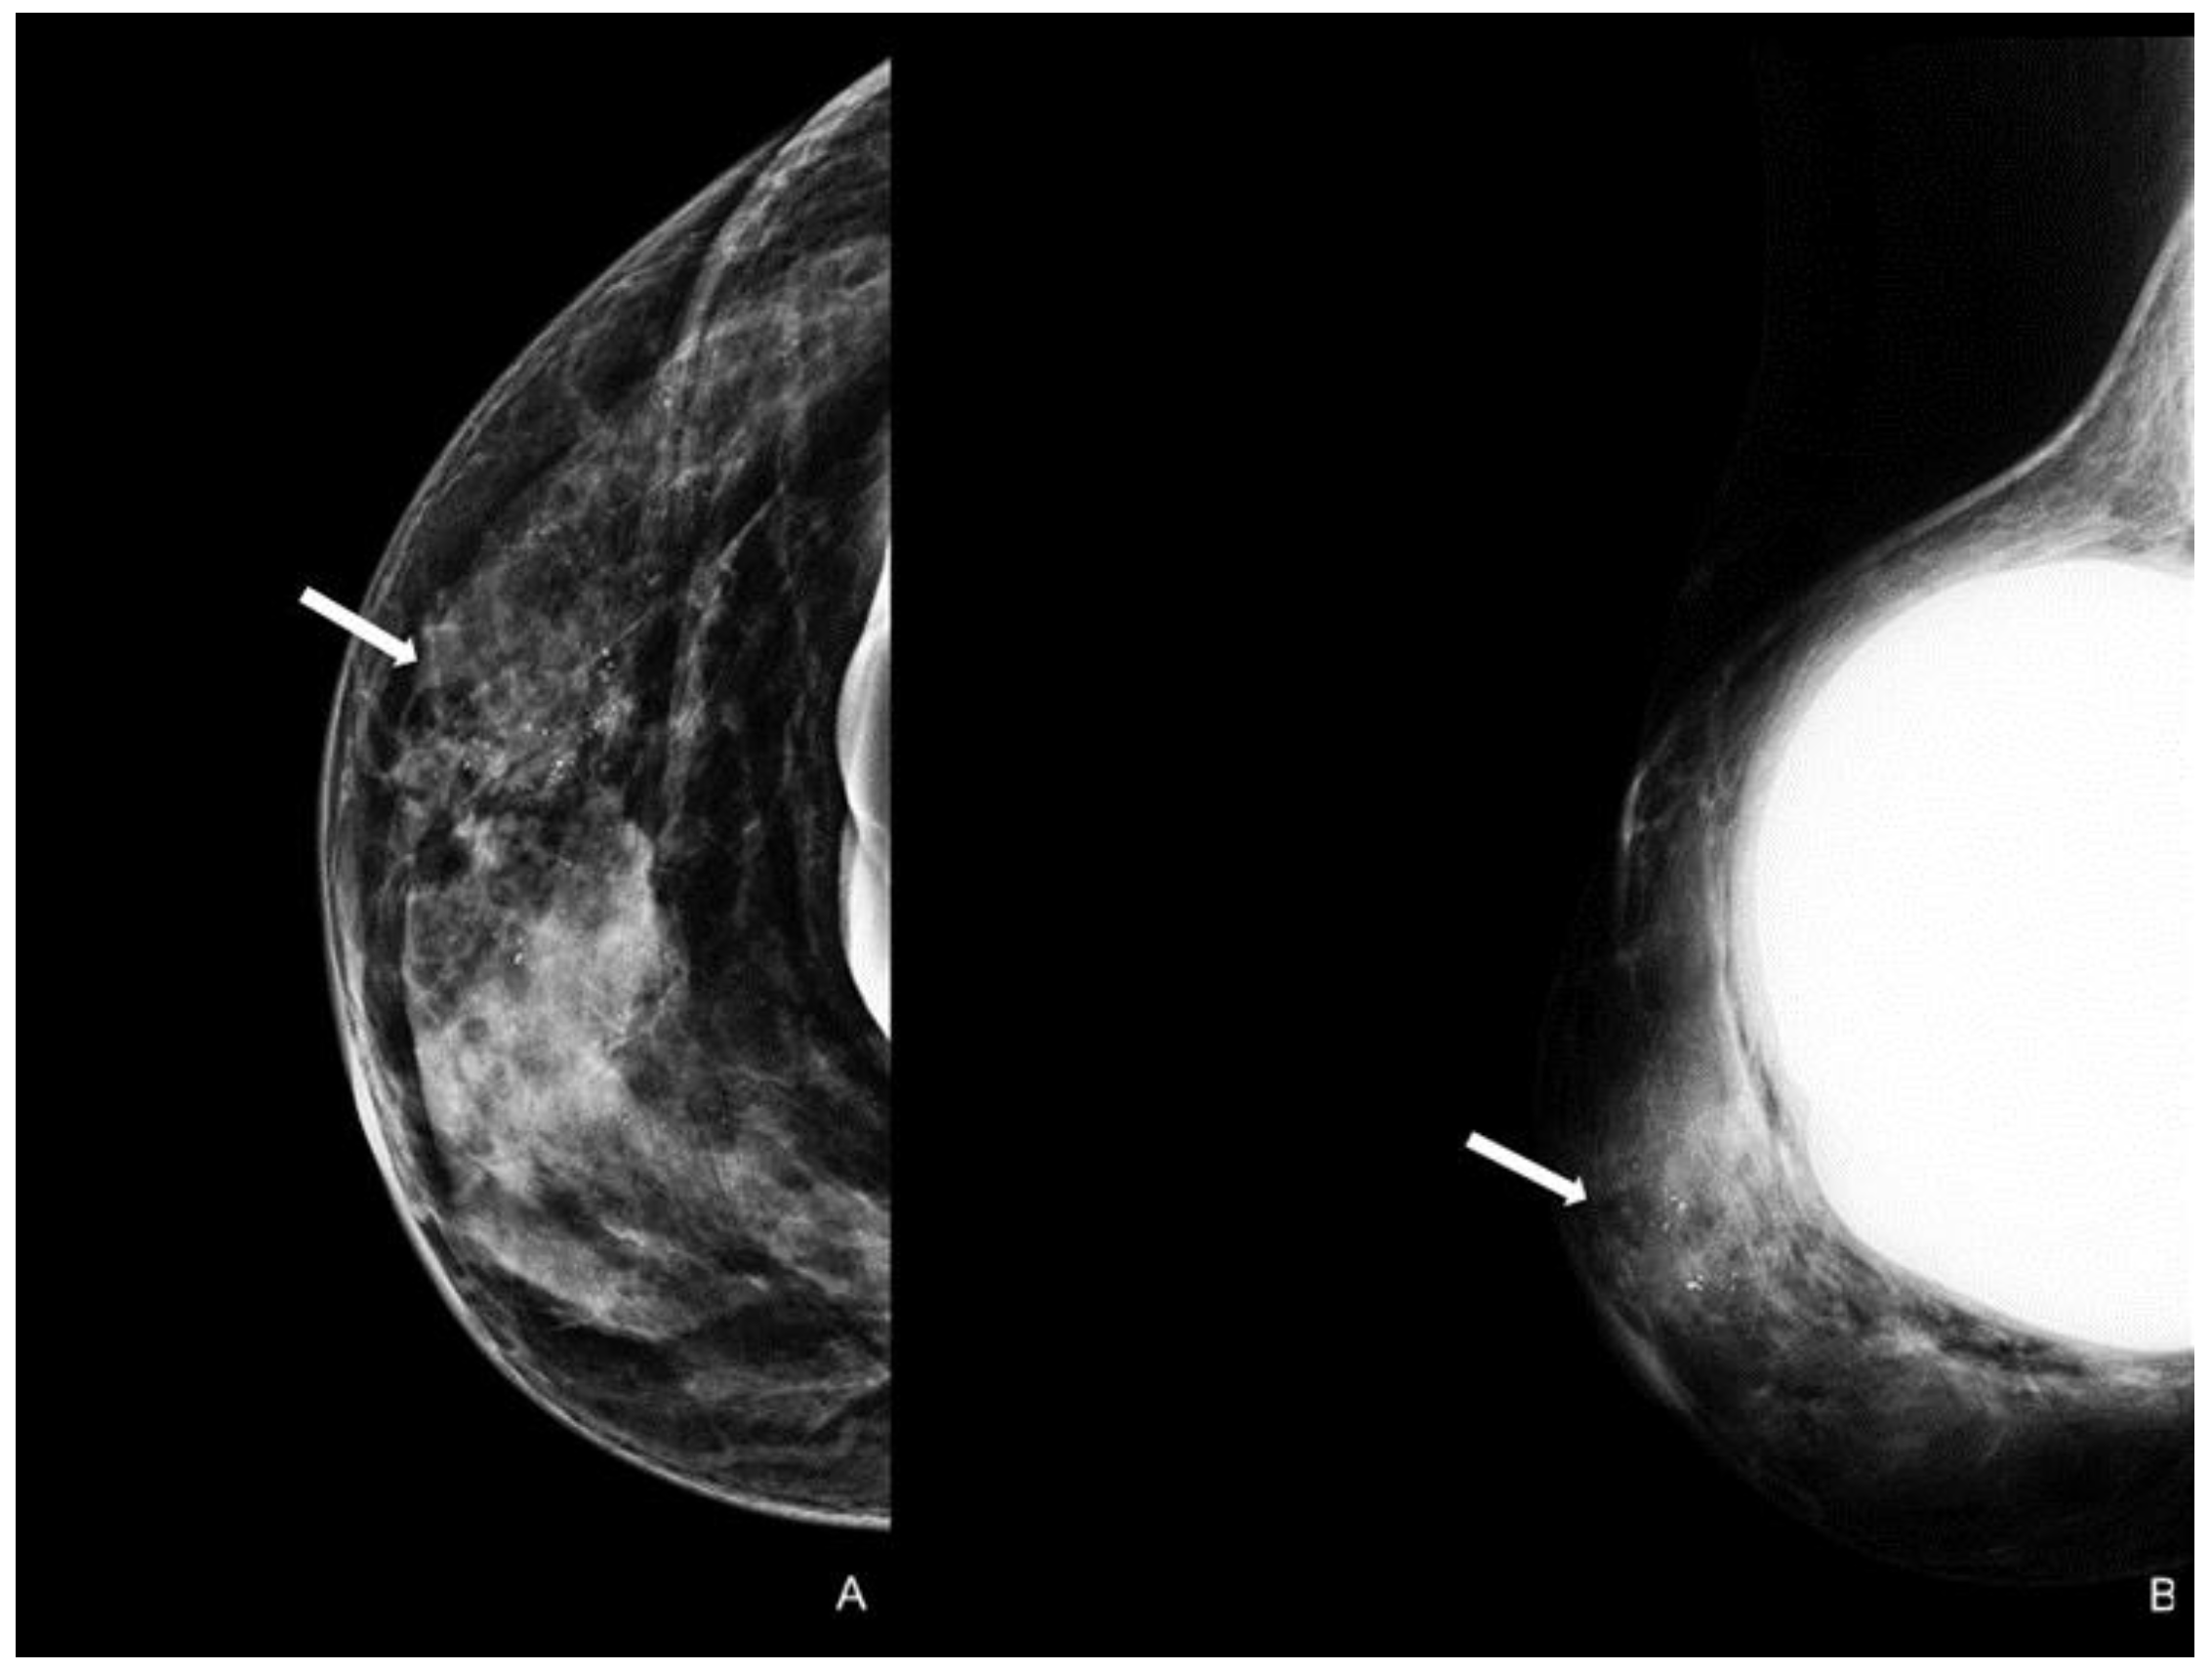

Figure 4.

Woman with a bilateral breast augmentation and a history of recurrent eczema of the right nipple. A skin biopsy was performed, and MPD was confirmed. Unilateral craniocaudal (A) and oblique (B) mammograms of the right breast show periareolar skin thickening and diffuse fine pleomorphic microcalcifications (arrow). The patient underwent a stereotactic biopsy and was diagnosed with high-grade in situ ductal carcinoma.